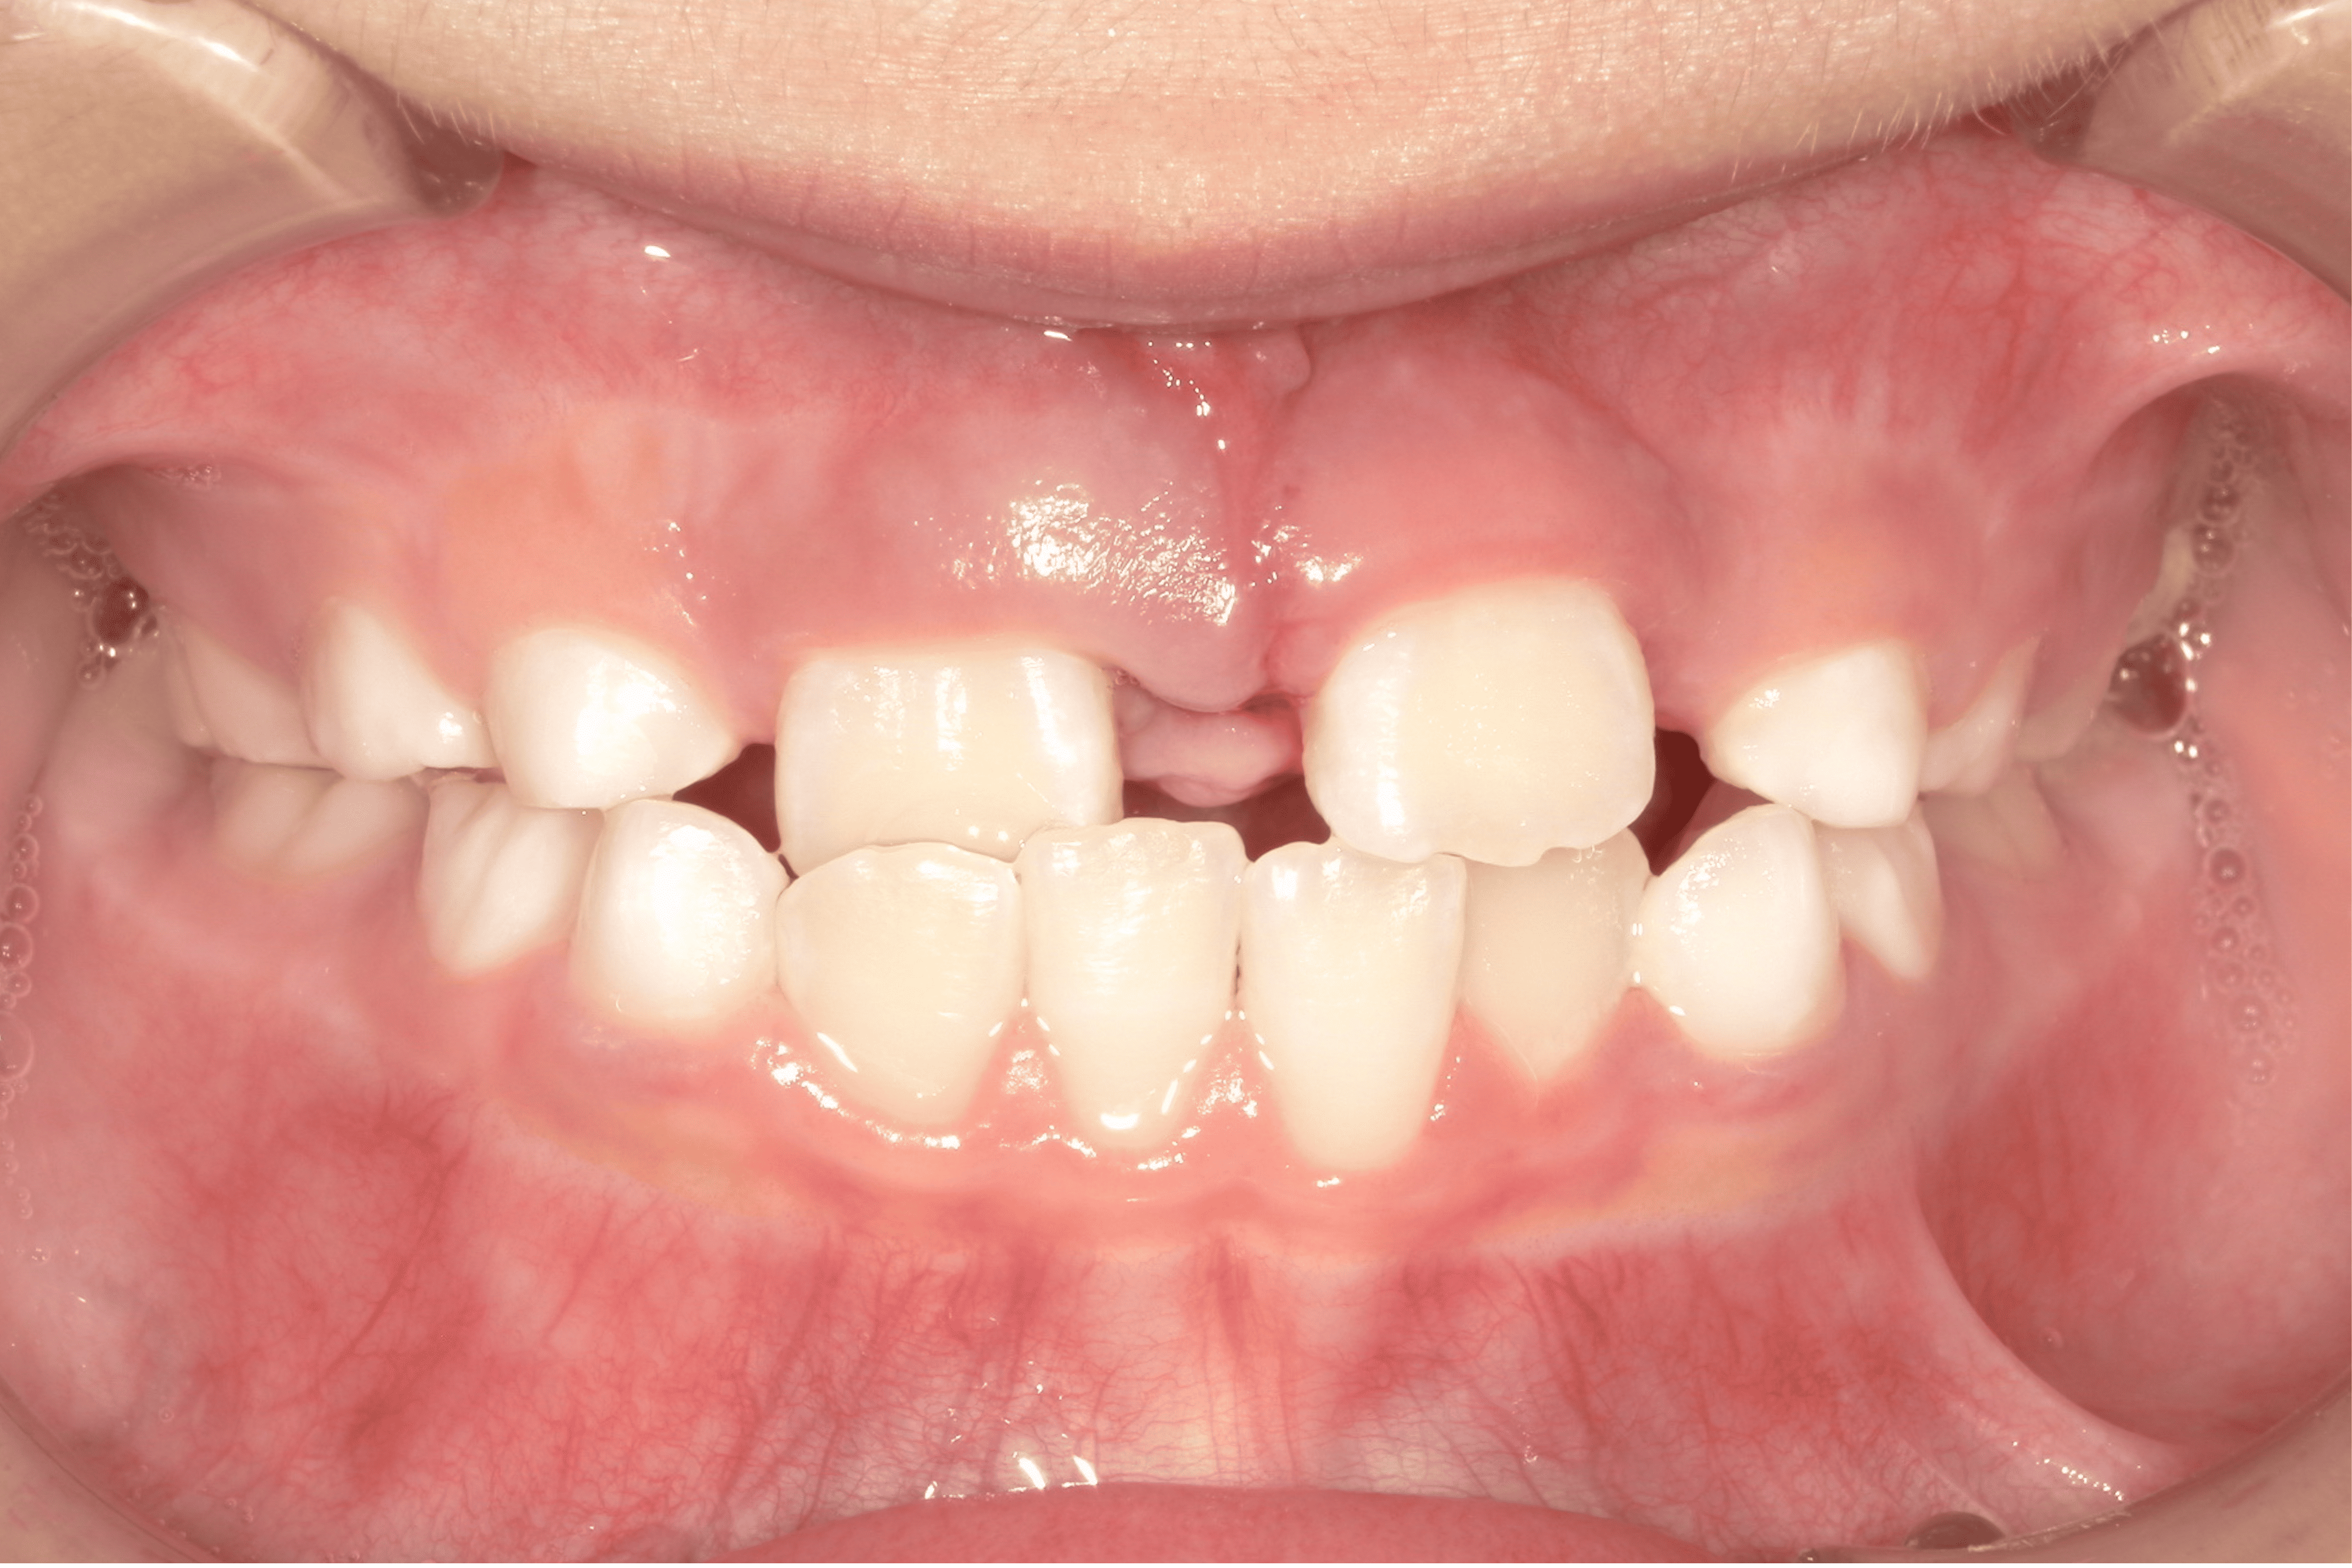

歯並びが気になる男の子の症例

Before

After

| 患者様の主訴 | スペース不足による叢生 |

|---|---|

| 治療内容 | バイオネーター |

| 治療期間 | 1年間 |

| 治療費用 | 330,000円(税込) |